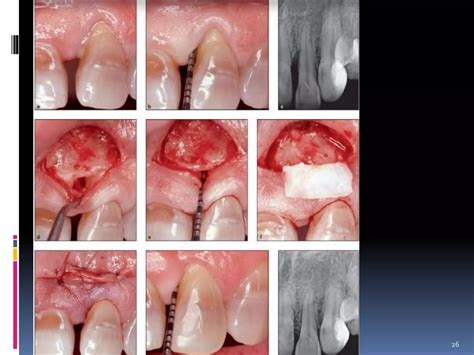

Soft Tissue Grafts Techniques | PPT

Soft Tissue Grafts Techniques | PPT